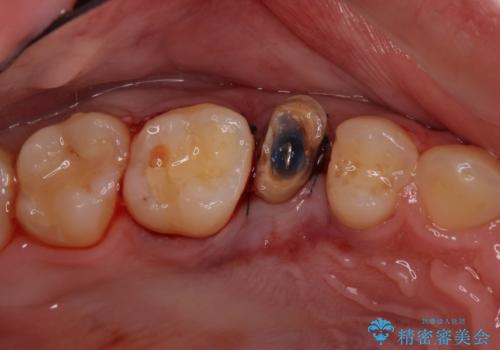

他院で虫歯治療を複数行っており、原因となりうる歯がいくつかありました。まずレントゲン上最もあやしい右上から治療開始しました。

右上の被せものを除去したところ、中で歯が割れていたため、部分矯正で引っ張り出すことになりました。

・歯肉が落ち着いてから最終的な被せものの製作となります(約3か月)。